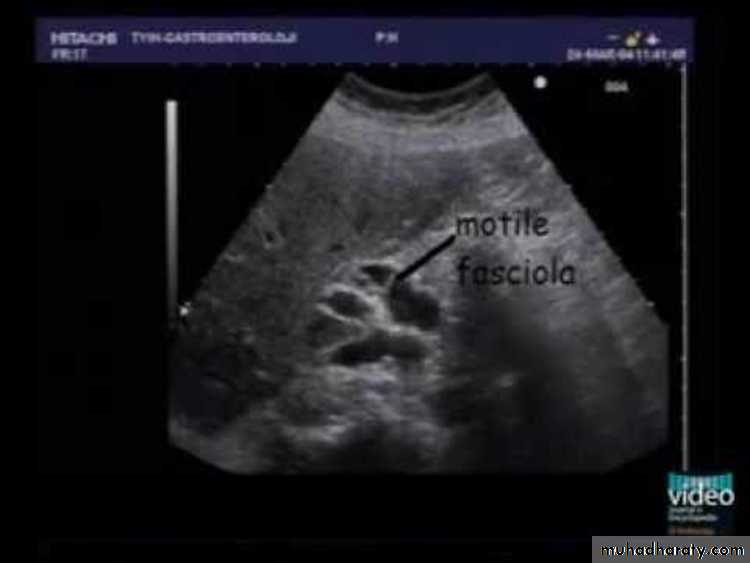

Ultrasound ,and CT scan .